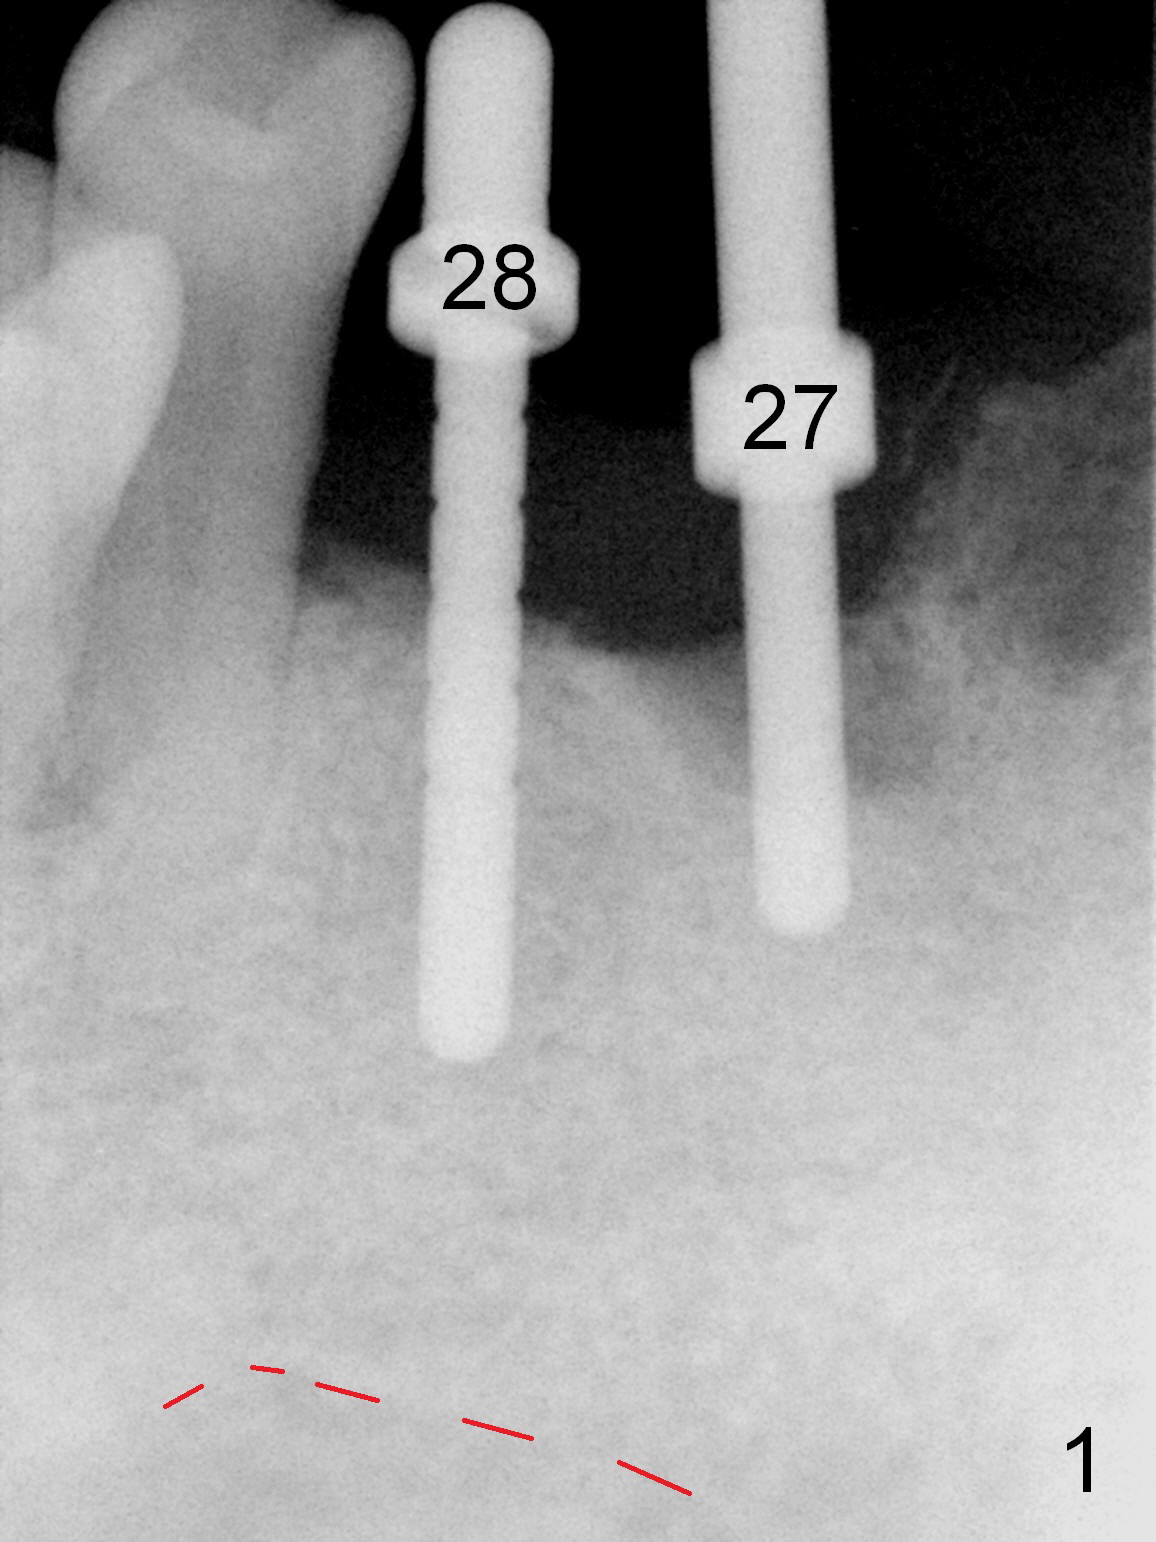

As expected, the bone density in the mandibular anterior region is found to be high during initial osteotomy (Fig.1-3).  Five implants are placed at the sites between #22 and 28 (Fig.4,5): 3x14(2) mm 1-piece (bone-level) implants in the incisor region; 4.5x17 mm 2-piece (tissue-level) ones in the canine/premolar area.  All of the implants are placed as lingual as possible.  Bone graft is placed (*).  Red dashed line: the superior border of the Inferior Alveolar Canal.  Immediate splinted provisional bridge is fabricated.  One week postop, periodontal dressing remains attached to the provisional and the gingiva.